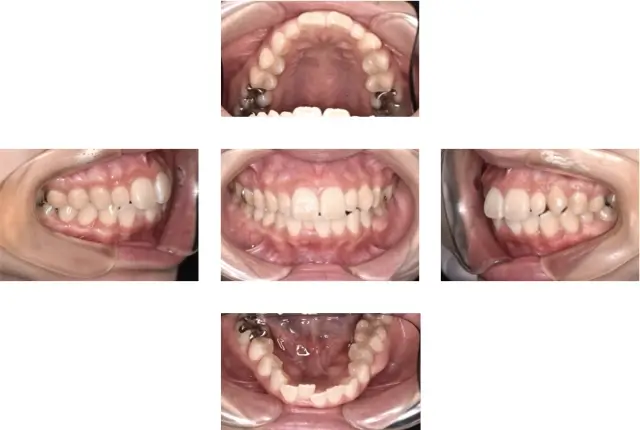

出っ歯(上顎前突)治療 2

初診時年齢 11歳6ヶ月 主訴 口が閉じれない

診断名 上顎前突 治療に用いた主な装置 マルチブラケット装置

抜歯部位 抜歯(上下顎左右側4番抜歯) 治療期間/回数 2年4ヶ月/28回

費用の総額 1,089,000円(税込) 費用内訳